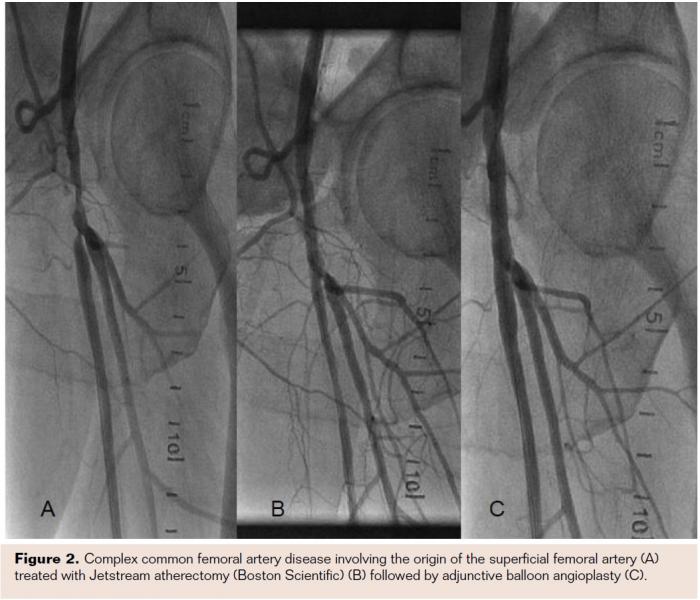

Modifying or debulking calcium is now the target of several therapeutic modalities, and studies are emerging to investigate the impact of calcium on procedural and long-term outcomes following endovascular therapies. Debulking in general has been associated with improving vessel compliance and reducing dissection and bail-out stenting, as demonstrated by the pilot single-center randomized trial of angioplasty vs directional atherectomy followed by adjunctive balloon angioplasty.12 This early observation was then tested in a multicenter randomized trial, the CALCIUM 360° study,13 which applied orbital atherectomy with balloon angioplasty vs balloon angioplasty alone in popliteal and infrapopliteal severely calcified vessels in predominantly critical limb ischemia patients. The study duplicated the same earlier findings despite the presence of severe calcification. In this study, adjunctive balloon angioplasty post orbital atherectomy led to a likely change in vessel compliance as indicated by the reduction in the average maximum balloon pressures required to obtain full balloon inflation post atherectomy (5.9 atm vs 9.4 atm, P<.001), a trend toward higher procedural success (93.1% vs 82.4%), fewer dissections (3.3% vs 11.4%) and bailout stenting (6.9% vs 14.3%), and a higher freedom from revascularization (93.3% vs 80%). Interestingly, a statistically significantly higher freedom from major adverse events in the orbital atherectomy arm (93.3% vs 57.9%, P=.006) was seen. Applying the same concept to moderately and severely calcified superficial femoral artery in the COMPLIANCE 360° trial,14 orbital atherectomy again confirmed the impact of debulking on improving vessel compliance, reducing dissection (15.8% vs 48.1%, P=.02) and bail-out stenting (5.3% vs 77.8%, P<.001) and a trend toward a higher freedom from revascularization (81.2% vs 78.3%). Several prospective registries also demonstrated the low dissection and stenting rate post debulking with various debulking devices, confirming the findings of these proof-of-concept randomized trials (Figure 2).16-18

In addition to orbital atherectomy, there are several other devices that can modify or remove calcium. The Turbohawk catheter (Covidien) was designed to cut into calcified plaque. In the DEFINITIVE Ca study, the pivotal registry that led to the approval of the Spider Filter in calcified superficial femoral arteries when used with the TurboHawk, dissection rate was low at 0.8% (type D and higher) and stenting was only 4.1%.17 In addition, the Jetstream atherectomy device (Boston Scientific) has also been shown to be very effective in debulking calcium and fibrotic tissue. In a small, prospective, IVUS-based analysis that included moderately to severely calcified femoropopliteal arteries, Jetstream increased minimal luminal area (MLA) from 5.1 to 8.3 mm2 and reduced area stenosis from 64% to 41%, and the decrease in calcium area (2.8 mm2) at the lesion level accounted for 86% increase in the lumen area.19 In the prospective, single arm, Pathway PVD multicenter trial, 172 patients at 9 European centers were treated with the Jetstream device (early generation).16 Device success was 99% (208/210 lesions). Eighty-five percent of patients were TLR free at 6 months and 74% were TLR free at 12 months. Stenting was performed in 7% of lesions. Given the data from several small randomized trials and registries, the evidence points to atherectomy as an effective tool to modify or remove calcium, hence improving vessel compliance and reducing dissections, resulting in an overall higher procedural success without the need for bail-out stenting. Although the data suggest a trend toward improving TLR rates with debulking, this has not yet been proven in a well-powered study, and the advent of DCB is likely to make this relatively small possible gain irrelevant.